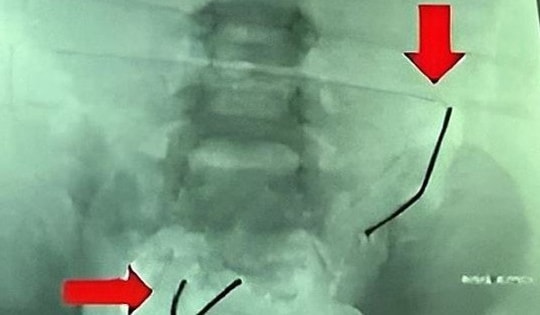

Bé trai 4 tuổi đau bụng dữ dội, nôn ói, bác sĩ gắp ra thứ "đáng sợ" bên trong

05/10/2025 11:01

Bé trai 4 tuổi ở Tp.Cần Thơ nhập viện trong tình trạng đau bụng dữ dội, bụng chướng, nôn ói nhiều, có dấu hiệu nhiễm trùng nặng.

Bé trai 5 tuổi đau bụng, nôn ói, gia đình đưa đi kiểm tra thì sốc nặng

04/09/2025 18:41

Bé 5 tuổi nôn ói, đau bụng nhiều. Tại bệnh viện, bác sĩ phát hiện thủng 8 lỗ ở ruột non, lấy ra 2 chuỗi viên nam châm tổng cộng 20 viên.